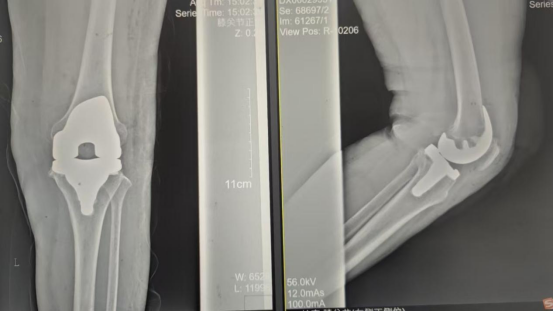

術前影像資料

因張女士患有高血壓病2級(高危)、心律失常(竇緩)且伴有肺部感染等并發癥。穆志亮主任和葉龍安主治醫師根據張女士的病情制定詳細手術方案,建議在全麻下行“左人工全膝關節置換術”。

手術當天張女士懷著忐忑的心情進入手術室,然而伴隨著麻醉醫師的和藹交談和手術護士的溫馨叮嚀,在不知不覺中慢慢睡著,手術非常順利。術后經醫護人員的精心治療與護理,張女士康復出院,最終解決了10余年的病痛。

術后影像資料